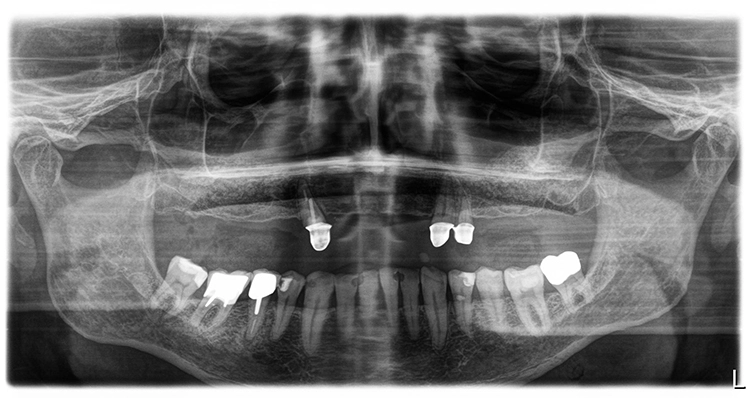

Nach einer – aufgrund eines Campingurlaubs von sechs auf acht Monaten – verlängerten Heilphase konnte der Patient implantiert werden. In der Röntgenkontrollaufnahme zeigten sich stabile knöcherne Strukturen in den augmentierten Bereichen des Sinus. Die Insertionen erfolgte gemäß Protokoll frei Hand auf Grundlage der DVT-Aufnahme und orientiert an der alten Teleskopprothese.

Der Therapieplan wurde in Abstimmung mit dem Patienten erstellt. Dabei war zu berücksichtigen, dass der Patient über den gesamten Behandlungszeitraum bis zur Fertigstellung der definitiven Restauration unbedingt kaufunktionell versorgt zu bleiben wünschte, da er zwischenzeitlich in Campingurlaub gehen wollte. Aufgrund der starken Pneumatisation der Kieferhöhlen wurden im posterioren Bereich beidseitig ein externer Sinuslift und nach Ausheilung der Strukturen die Implantation von sieben Implantaten (Conelog, Camlog, Wimsheim) mit unterschiedlichem Durchmesser und je 13 mm Länge geplant.

Die Implantatmaße und -positionen sowie der Umfang der Sinusbodenelevation wurden dabei in Sinne eines „backward planning“ anhand von DVT-Aufnahmen bestimmt. Zahn 13 sollte noch vorübergehend erhalten bleiben, um zusammen mit den bleibenden Zähnen 23 und dem entsprechend kariesbehandelten Zahn 24 bis zur Fertigstellung der definitiven Restauration der alten Teleskopprothese als Interimsersatz Halt zu geben. Als definitive Versorgung wurden drei VMK-Brücken auf NEM-Gerüsten vorgesehen. Damit sollte auch die natürliche Bezahnung im Unterkiefer von 37 bis 47 abgestützt werden.